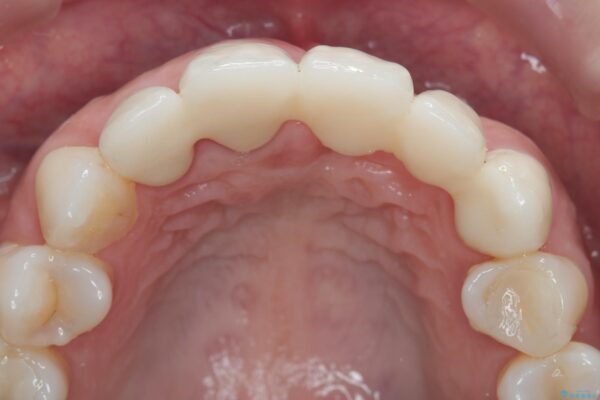

一見して問題ないように見える左側の2前歯は、セラミックを除去してみると亀裂や虫歯の再発が見られました。

一件綺麗に見えるセラミックも適合や精度が悪いと、内部で虫歯が進行し亀裂や破折、悪臭の原因となることがあります。

治療後

歯槽堤保存術を併用したブリッジ治療 治療後画像 歯槽堤保存術を併用したブリッジ治療 治療後画像 歯槽堤保存術を併用したブリッジ治療 治療後画像 歯槽堤保存術を併用したブリッジ治療 治療後画像 歯槽堤保存術を併用したブリッジ治療 治療後画像 歯槽堤保存術を併用したブリッジ治療 治療後画像 歯槽堤保存術を併用したブリッジ治療 治療後画像